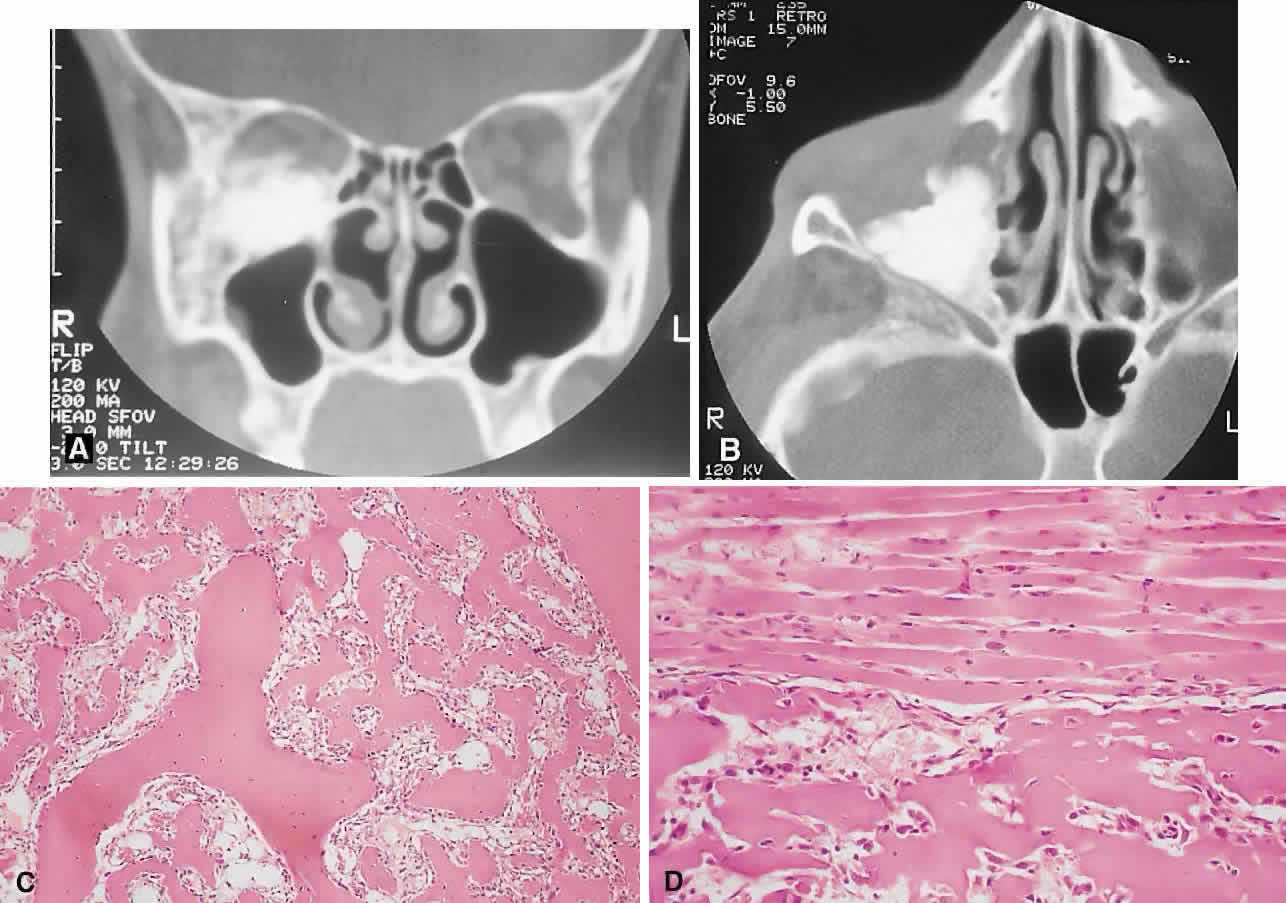

clinicopathologic classification (see Table 1). BENIGN FIBRO-OSSEOUS AND CARTILAGINOUS LESIONS Osteoma A true osteoma is a tumor-like mass of bony tissue that is histologically similar to normal bone. Its pathogenesis remains unclear, although traumatic, infective, or hamartomatous theories have been proposed.4 Others have suggested that osteomas arise exclusively at the junction of bones of cartilaginous and membranous origin.5 None of these theories account for the facts. The most common sites of origin are the paranasal sinuses, skull, and facial bone. The fact that osteomas were found in 0.42% (15 of 3510) of plain sinus radiographs reflects their prevalence.6 In the sinuses, 50% occur in the frontal sinus, with the ethmoid, maxillary, and sphenoid involved in descending order of frequency. Most orbital osteomas are secondary invaders from adjacent sinuses, but on occasion they arise primarily in the orbit. In contrast to the sinus distribution, however, orbital osteomas appear to have a roughly equal origin from the ethmoid, frontoethmoid, or frontal regions.7,8 This may reflect the relatively thin barrier to expansion posed by the medial orbital wall. The age range runs the gamut from 10 to 82 years, with the highest prevalence in the fourth and fifth decades. Males and females are represented equally.7–9 PRESENTATION. Most sinus osteomas are solitary and asymptomatic.6 However, when large enough to encroach on the orbits, a gradual evolution of proptosis or globe displacement over many years can occur (Fig. 1). There may be an associated headache as a result of expansion of the overlying cortex and periosteum, and a bony mass is often palpable in the superior or superomedial orbit. Obstruction of the sinus ostia may lead to chronic sinusitis or mucocele. Less common features include an acquired Brown syndrome,10 gaze-evoked amaurosis or pain,4,11 subluxation of the eye12 and erosion leading to orbital emphysema, or cerebrospinal fluid rhinorrhea.13 The sphenoid sinus, although a rare site, is significant because even a small lesion may lead to an orbital apex syndrome. An uncommon but important systemic association is Gardner's syndrome. This autosomal dominant syndrome of osteomas, soft tissue tumors, and peripheral congenital retinal pigment epithelial hypertrophy also includes the development of colonic polyposis with subsequent malignant transformation.14–16 Multiple osteomas are common; our one patient had only a single tumor, but one was also noted in the skull. Further, because bony lesions may predate the colonic pathology, patients with osteoma warrant a dilated funduscopy and referral to a gastroenterologist.17 IMAGING. The plain radiograph and CT appearances consist of an osteoblastic round or ovoid sharply circumscribed mass, usually arising in the sinus and invading the orbit. Tumors growing in a sinus conform to its internal contour and often have a bosselated surface. Osteomas may be sessile or pedunculated and generally have a diameter of 1 to 5 cm.18 Bone window settings on CT imaging often show a very dense periphery with a more cancellous internal structure. However, the relative proportions of the two densities may vary with the size of the lesion. HISTOPATHOLOGY. It is important to distinguish osteomas from reactive osteomatous responses to infection, trauma, and chronic inflammation. The clinical and radiologic appearances are often invaluable in this regard. Macroscopically, true osteomas have smooth or bosselated contours with a glistening white or pinkish coloration. A covering of mucoperiosteum or periorbita may be seen, depending on the site of origin.18 Osteomas have been classified histologically into three groups depending on the predominant tissue present: compact (cortical, ivory), cancellous (trabecular, spongy), and fibrous. Fu and Perzin19 have postulated that the histologic type is partly dependent on the age of the lesion, with the compact group representing the most mature and the fibrous the least. The fibrous subtype may, in fact, be part of a continuum incorporating ossifying fibroma and fibrous dysplasia. The compact areas resemble normal cortical bone with dense bony areas and haversian systems. However, there are subtle differences in the arrangement of the haversian canals, which is often evident to the experienced bone pathologist. The cancellous areas consist of anastomosing trabeculae with an intervening fibrovascular stroma. Fatty and hematopoietic elements may also be present in the stroma, as well as evidence of osteoblastic activity along the trabeculae. The fibrous region is made up primarily of loose fibrovascular tissue with a few irregular bony trabeculae and osteoid elements. In our series of nine surgically treated cases, we noted that although the three types of tissue were present in varying admixtures, in all cases there was a remarkably consistent pattern of arrangement. The most peripheral zone was made up of compact bone; moving toward the center or base of the lesion, there was an intermediate zone of increased osteoblastic activity, osteoid, and vascularity. The innermost region consisted of a loose fibrous stroma with a greater number of blood vessels, few trabeculae, and many plump osteoblasts. This configuration has been described previously by Albert and associates20 and illustrates the growth of these lesions. The outermost zone presumably represents more mature bone, and the activity seen centrally suggests that this is where growth is initiated. This implies that extirpation of the central region is probably required to prevent recurrence. It may also explain why leaving residual peripheral areas does not usually lead to regrowth. Finally, the histologic subtyping into compact, cancellous, and fibrous lesions probably has little practical significance, because there appears to be no correlation with the clinical course. MANAGEMENT. Generally, asymptomatic osteomas can be treated conservatively. The only possible exception to this is in the sphenoid sinus: it is technically easier to remove a small lesion in this location before it has encroached on the orbital apex and optic canal. If symptomatic and located in the anterior orbit, osteomas can be removed through an anterior orbitotomy. For anterior ethmoid tumors in the superomedial orbit, a modified Lynch incision is often used. Excision can sometimes be aided by coring the lesion and collapsing the cortex for removal. For more posterior tumors, involving the roof or cribriform plate, a combined orbitocranial approach using a bicoronal incision is favored.21 Recurrence is rare, even after a partial resection. Fibrous Dysplasia Fibrous dysplasia is a benign disorder in which proliferation of fibrous tissue and osteoid replaces and distorts medullary bone. The cause is unknown; past theories have included a maturation arrest at the woven bone stage, or hamartomatous proliferation.22 More recently, the discovery of a postzygotic mutation in the G protein in McCune-Albright syndrome suggests that the bone dysplasia in these patients is a manifestation of a somatic mosaic state.23,24 There are three forms of fibrous dysplasia: monostotic fibrous dysplasia (MFD), polyostotic fibrous dysplasia (PFD), and McCune-Albright syndrome.22,25 MFD accounts for 75% to 80% of cases, of which 20% affect the craniofacial bones. In the skull, the frontal bone is most commonly involved, followed by the sphenoid and ethmoid. Most patients with orbital involvement have MFD, although the disease has generally spread to contiguous bones by the time the patient comes to medical attention. PFD makes up 20% of all cases; half of these patients have head and neck involvement. McCune-Albright syndrome occurs largely in females and incorporates the triad of PFD, sexual precocity, and cutaneous pigmentation.26 This pigmentation appears as brown macules, usually six or fewer, with irregular “coast of Maine” borders.27 Fibrous dysplasia is generally recognized before age 30, although mild or asymptomatic cases may escape detection into late adult life.28 The gender distribution is roughly equal in MFD; there is a female predilection in PFD. PRESENTATION. The site and the extent of disease are the major determinants of symptomatology. Facial asymmetry, proptosis, and globe displacement evolving over many years are the most common manifestations (Fig. 2). Nasolacrimal duct blockage, diplopia, nasal obstruction, malocclusion, raised intracranial pressure, and cranial nerve palsies also occur.25,28–30 Acute or subacute compressive optic neuropathy can arise as a result of intralesional hemorrhage, sphenoidal mucocele, or secondary aneurysmal bone cyst.31 A more chronic visual loss, although less commonly reported, may occur as a result of compression in the optic canal or at the chiasm. On occasion, a superimposed ischemic neuropathy in the context of chronic compression leads to an acute on chronic deterioration in vision.32 This clinical spectrum is reflected in our experience of 10 cases. Changes in facial contour (7 patients), proptosis (7), globe dystopia (6), and decreased vision (3) were the major signs. Interestingly, seven patients also had pain, either localized to the orbit or described as a diffuse ipsilateral headache. Overall, the natural history is one of slow growth. Although this was previously thought to cease in adult life, there is evidence that fibrous dysplasia may progress well past the fourth decade.25 Rarely, malignant transformation to osteosarcoma, fibrosarcoma, chondrosarcoma, and giant cell sarcoma can occur; this is often signaled by a more rapid progression and increased pain. The incidence of this complication is estimated at 0.4% to 0.5%, rising to approximately 15% with prior radiation therapy.33 IMAGING. In the craniofacial bones, fibrous dysplasia tends to expand the bone, with thinning of the overlying cortex. The margins are poorly defined, and the dysplasia transgresses suture lines; the proportion of mineralized to fibrous tissue determines the degree of radiolucency. Most cases demonstrate a relatively equal mixture, resulting in a pagetoid appearance. Where the fibrous element is predominant, there may be cystlike areas; a preponderance of mineralized tissue, however, results in a homogeneous, sclerotic, “ground-glass” picture. Fries34 reviewed 39 patients with fibrous dysplasia of the craniofacial bones and found a pagetoid pattern to be most common (56%), followed by sclerotic (23%) and cystlike (21%) appearances. The primary differential is hyperostotic meningioma. This is distinguished by its occurrence in an older age group and by the presence of an associated enhancing soft tissue component, best seen on MRI. Also, meningioma often causes a more homogeneous thickening of bone, which in contrast to fibrous dysplasia does not leave a discernible cortical rim. MRI shows meningioma to have a signal isointense to gray matter on both T1- and T2-weighted images. Fibrous dysplasia, in contrast, tends to have a lower intensity on T1- and a heterogeneous signal on T2-weighted images.28,35 MRI may also have a role in fibrous dysplasia in the evaluation of mucoceles and recent hemorrhage. On occasion, Paget's disease and less commonly cystic bone lesions, such as localized Langerhans cell histiocytosis (eosinophilic granuloma), also enter into the differential diagnosis. Paget's disease arises beyond the age of 40, is usually bilateral, and radiologically may show areas of cotton wooltype density that are not usually seen in fibrous dysplasia. HISTOPATHOLOGY. Macroscopically, fibrous dysplasia consists of gritty, white-to-pink tissue, often with blood or serous-filled cystic areas. Histologically, there is a fibrous background containing trabeculae of woven bone. The stroma has variable amounts of collagen, fibroblasts, and vascularity. There may also be myxomatous areas and secondary aneurysmal bone cysts. The curvilinear bone trabeculae take on a variety of configurations, including C or Y shapes (so-called Chinese characters). These trabeculae sometimes have irregular margins as a result of the attachment of collagen fibers arising in the stroma. Cartilaginous nodules as well as small foci of lamellar bone are occasionally seen, but the vast majority of lesions contain immature woven bone. At its periphery, fibrous dysplasia permeates normal bone, and there may be areas of reactive bone with more prominent lamellar bone formation and osteoblastic rimming. Sequential biopsies of fibrous dysplasia from childhood to adult life have shown that the histologic picture does not change with time.36 In the skull, the major histologic differential is ossifying fibroma. The latter, however, is a more circumscribed lesion that displays prominent production of lamellar bone with osteoblastic rimming. MANAGEMENT. Traditionally, there has been a conservative approach to surgery for fibrous dysplasia, with intervention reserved for gross deformity, functional deficits, pain, or sarcomatous transformation. The procedures included resection if the lesion was well localized, curettage with bone grafting, or contouring. The last two decades have seen a shift to more aggressive and earlier intervention. A multidisciplinary craniofacial approach has been advocated, wherein as much affected bone as possible is removed and the resulting defects are reconstructed in a single operation.37 The indications for intervention include those previously mentioned, with the added rationale of attempting to prevent complications such as optic nerve compression.23,38 However, long-term follow-up data comparing outcomes with the natural history of the disease are lacking. Also, there have been two reports of blindness complicating prophylactic optic nerve decompression.25,32,39 Thus, the need for prophylactic treatment remains unresolved; it is not recommended unless a functional deficit develops. Ossifying Fibroma There is controversy as to whether ossifying fibroma is a distinct clinicopathologic entity: some authors believe it is a variant of fibrous dysplasia.40 Nevertheless, there appear to be enough disparate features to characterize it as a benign fibro-osseous neoplasm. Ossifying fibroma occurs most commonly in the mandible in the first two decades of life, with a proclivity for females. Only rarely does it arise in the orbit, with the frontal bone being most commonly involved, followed by the ethmoid and the maxillary bones. There are 37 orbital cases reported in the literature, with an age range of 4 months to 52 years and an approximately equal male/female ratio.12,19,41–50 PRESENTATION. As a result of its slow growth, ossifying fibroma generally manifests as a gradual painless globe displacement, with a temporal course measured in years. The mass effect may also lead to proptosis, diplopia, and, if situated more posteriorly, compression of apical structures. IMAGING. Ossifying fibroma starts as a monostotic lesion that expands the bone of origin in a well-circumscribed manner. However, with growth it may spread to involve adjacent bones and may even extend across the midline to involve both orbits. The characteristic CT appearance is of a round or ovoid mass with a well-defined, thin sclerotic margin (Fig. 3). Centrally, there is often a patchy pattern of osteoblastic and osteolytic areas.46 HISTOPATHOLOGY. Macroscopically, the lesional tissue is white to red and has a largely soft fibrous texture with variable grittiness, dependent on the amount of osteoid. Microscopically, it consists of a cellular vascular stroma containing trabeculae of lamellar bone. These bony trabeculae often have a thin surrounding of osteoid and, in contrast to fibrous dysplasia, display prominent osteoblastic rimming. There may also be osteoblasts as well as a few foci of giant cells in the stroma. If larger specimens are available, they may demonstrate a zonation phenomenon, seen as an increasing maturity of bone toward the periphery.19 In the psammomatoid variant described by Margo and colleagues,49 at least half of the tumor contains sphericular ossicles. This histologic pattern has been correlated with a more aggressive local behavior and a tendency to recur after incomplete excision. MANAGEMENT. The natural history of ossifying fibroma is one of inexorable progression; thus, surgical intervention is generally required. Because the propensity for recurrence after incomplete excision is well recognized, the surgical objective should be complete removal. This is particularly applicable in the psammomatoid variant. For anterior, relatively small lesions, this may be achieved using a percutaneous or bicoronal approach. However, most tumors tend to be sizable (5 cm in diameter) at presentation.49 Thus, for these lesions as well as those located more posteriorly, combined orbital, neurosurgical, and rhinologic approaches are usually necessary.45 Osteoblastoma Osteoblastoma is a benign tumor composed of osteoblasts that produce osteoid and bone. It usually arises in the vertebrae and long bones, and its occurrence in the craniofacial region is extremely rare. These tumors are most commonly seen in the second and third decades and have a male/female ratio of 2:1.51 Seven cases with orbital involvement have been reported in the past 30 years.19,52–57 In four of these, the tumors appeared to arise from the orbital roof, with the remainder originating in the ethmoid sinuses. The natural history is of slow growth, although a minority display a more aggressive behavior (aggressive osteoblastoma). PRESENTATION. The presentation in all patients was of a slowly progressive mass effect with proptosis and either downward or outward displacement of the globe. Pain or discomfort was a feature in several patients. IMAGING. In the long bones, osteoblastomas produce cortical expansion and have a lytic center. They can also simulate a large osteoid osteoma, with a lucent halo and central ossification. The different morphology of the orbital bones means that the tumor appears as an osteolytic lesion with a sclerotic margin; it occasionally has ossification of the matrix.51 HISTOPATHOLOGY. The gross appearance is of a relatively gritty or friable, reddish-brown tissue. There is a broad spectrum of histologic appearances. The typical picture is of a network of osteoid trabeculae with osteoblastic rimming. These osteoblasts generally have abundant cytoplasm and regular nuclei. However, in some tumors, large epithelioid osteoblasts or a pseudosarcomatous appearance can be observed; this can lead to confusion with osteosarcoma.58 In contrast to osteosarcomas, however, even atypical osteoblastomas show a tendency toward peripheral maturation and do not permeate surrounding bone. Some authors have suggested that this atypical appearance may correlate with a more aggressive clinical course and have used the term aggressive osteoblastoma to define a separate clinicopathologic entity. It is a rare variant, with only one case being reported in the skull.59 The histology of osteoblastoma is similar to that of osteoid osteoma, with the latter being distinguished by a size smaller than 1.5 cm as well as a somewhat less cellular and vascular stroma.60 Nevertheless, they may represent a spectrum of disease, a fact somewhat supported by the recent finding of a common clonal chromosomal abnormality in both tumors.61 Osteoid osteoma, however, has not been reported in the orbit. MANAGEMENT. Excision is generally curative; however, there is one report of recurrence of an orbital tumor after a piecemeal removal.56 There have also been descriptions of a benign osteoblastoma of the skull that developed into an osteosarcoma after an incomplete excision,62 as well as a case of aggressive osteoblastoma of the temporal bone.63 In view of this, osteoblastomas should be completely removed under direct vision, where possible, to determine the margins. This usually entails an orbitocranial approach for tumors of the roof and a combined orbitorhinologic approach to those arising in the sinuses. Chondroma These benign cartilaginous tumors usually occur as asymptomatic lesions in the sinuses and nasal cavity. They rarely occur in the orbit, where they present as slow-growing, painless, firm lumps, often near the orbital rim or the trochlea.64,65 They have on occasion also been described in the soft tissues of the orbit.66 Radiologically, they are seen as well-circumscribed, dense masses that histologically consist of lobulated mature hyaline cartilage. Mature chondrocytes are seen in the cartilage, along with a variable fibrous or myxoid stroma. Surgical excision is always curative.64,67 A variety of other benign cartilaginous tumors, including osteochondromas, enchondromas (Fig. 4), and fibrochondromas, have also rarely been described in the orbit, although the histologic documentation is not always convincing.68 REACTIVE LESIONS Cholesterol Granuloma A cholesterol granuloma is a foreign body response to the presence of crystallized cholesterol. The common sites are the middle ear and pneumatized portions of the temporal bone.69 In the orbit, it occurs almost exclusively in the diploë of the frontal bone overlying the lacrimal fossa, although it has also been reported in the zygoma.70 Theories of pathogenesis include a purely traumatic intradiploic hematoma or a hemorrhage occurring in a pre-existing bony anomaly. A breakdown of blood products then leads to cholesterol deposition and a granulomatous response. An analysis of 75 reported cases of orbital cholesterol granulomas revealed a marked preponderance of men in the fourth and fifth decades of life.70,71 PRESENTATION. A superolateral mass effect encompassing weeks to years is the typical mode of presentation. This leads to inferior globe displacement, proptosis, and diplopia in upgaze (Fig. 5). There may be associated headache or pain; one third of patients recall a prior trauma.70,71 IMAGING. The granuloma arises in the diploë of the frontal bone, causing expansion and eventually erosion of the inner and outer tables. CT reveals it to be osteolytic, with a density equivalent to brain, and occasional intralesional bone fragments.72 Mature lesions display high T1 and T2 signal intensities on MRI.73,74 The most commonly evoked differentials in this setting are dermoid cysts and lacrimal gland carcinomas. HISTOPATHOLOGY. These cysts usually contain yellow-brown viscous material with friable tissue and porous bone at the periphery. Histologically, the principal feature is the dominance of cholesterol clefts surrounded by granulomatous inflammation with conspicuous foreign body giant cells. A variable fibrous stroma is present and usually contains extensive blood-derived debris in the form of extracellular and intracellular hemosiderin as well as more recent hemorrhage.70,75 There should be no evidence of epithelial elements, ruling out a diagnosis of epidermoid or dermoid cyst. The prominence of the xanthomatous components also serves to differentiate this condition from giant cell granuloma and aneurysmal bone cyst. We have seen six cases of cholesterol granuloma, two of which had histologic evidence of dysplastic-looking bone at their peripheries. This perhaps lends some support to the theory of a pre-existing dysplastic bony abnormality. MANAGEMENT. A percutaneous approach and curettage is almost always curative, with only one well-documented case of recurrence that occurred when peripheral bone containing lesional tissue was not removed.71 If there is an extensive intracranial component, a combined orbitocranial operation may be required.76 Aneurysmal Bone Cyst This benign cystic lesion occurs most commonly in the metaphyses of long bones and in the spine. The pathogenesis is not known, although 30% to 50% occur secondary to other bone diseases, including fibrous dysplasia, giant cell granuloma, giant cell tumor, osteoblastoma, osteosarcoma, and intraosseous hemangioma.18,77,78 There is also evidence that some aneurysmal bone cysts (ABCs) may arise as a reactive change to a pre-existing arteriovenous malformation.40 ABCs occur rarely in the skull; of those with orbital involvement, the frontal bone appears to be the most common location. An analysis of 24 recorded orbital cases, including 2 from our series, revealed an age range of 11 months to 42 years. Most presented in the second decade, and there was a female preponderance of 5:3.8,78–89 PRESENTATION. The usual signs and symptoms include proptosis, displacement of the eye, and diplopia. Masses in the midline can cause optic nerve compression.82 Because most ABCs arise in the orbital roof, intracranial extension can rarely give rise to raised intracranial pressure. Although typically subacute or chronic in evolution, sudden progression may occur as a result of intralesional hemorrhage.83 IMAGING. ABCs occurring in long bones have a characteristic uni- or multilocular expansile appearance. However, the radiology in the orbital bones is not specific and consists of destruction or expansion (Fig. 6). If expansile, the mass may have a thin cortical margin, but this is often absent as a consequence of erosion through to periorbita or dura. The central area is inhomogeneous, shows patchy enhancement, and can have multiple fluid levels, particularly in the more mature lesions.85,88 MRI may demonstrate recent hemorrhage in cases with an acute onset. HISTOPATHOLOGY. The gross specimen almost always consists of curettings of reddish-brown tissue with a texture that varies from friable to fibrous or gritty. More solid lesions may yield softer, pink to gray-white tissue. If larger samples are available, one may see honeycombed areas of serosanguineous or blood-filled cavitation.18,40 The cardinal microscopic features are cavernous blood-filled spaces that lack endothelial lining, pericytes, or smooth muscle. These spaces are bounded by a fibrous stroma that contains giant cells, hemosiderin-laden macrophages, lymphocytes, and trabeculae of osteoid and bone. The osteoid may lack osteoblastic rimming and may seem to arise from the stroma in a metaplastic fashion. Degenerating chondromyxoid areas may surround the osteoid and can display partial calcification.18,40 In 1983, Sanerkin and coworkers90 described a solid variant of ABC in which the aneurysmal sinusoids were either seen only in small foci or were absent. We have seen two cases that fit this histologic description. It is evident that this picture, apart from the chondromyxoid and sinusoidal foci, may bear a close resemblance to giant cell granuloma. Finally, in any case of ABC, one should conduct a meticulous search for a primary pathology such as fibrous dysplasia. MANAGEMENT. Curettage is typically curative. In the absence of an underlying bony abnormality, recurrence of orbital lesions is rare and usually occurs in the first 6 months.77,85 In such cases, a repeat curettage is generally successful. Resolution has also been reported after incomplete excisions. Radiation therapy has been used for recurrent aggressive lesions, but it entails a small yet definite risk of postradiation sarcoma.77 Giant Cell Granuloma Giant cell granuloma (GCG) is a benign granulomatous proliferation of unknown cause. It has also been called giant cell reparative granuloma, the term referring to a past theory postulating a reparative process in response to trauma and hemorrhage.91 GCG occurs most commonly in the mandible, maxilla, and phalanges.92 Cases with orbital involvement have been reported rarely and appear to have arisen in the maxilla, frontal, ethmoid, and sphenoid bones with equal frequency. Nine patients are reported in the literature and with the inclusion of our patient, they range in age from 5 to 54 years (average 18.6 years), and the male/female ratio is 3:2.93–98 This corresponds with the epidemiology of GCG elsewhere in the skeleton, which generally presents in the first two decades of life with an equal male/female ratio.94,96 PRESENTATION. Proptosis and ocular displacement are the most common presentations, although headache and pain may be prominent (Fig. 7). Diplopia and decreased vision also occur, depending on the site of the mass. The time course is variable, ranging from months to years, and may be complicated by a rapid progression of symptoms resulting from hemorrhage. IMAGING. GCG typically manifests as a destructive lesion with erosion of adjacent bone. It may have indistinct or sclerotic margins and may show moderate enhancement of an often-inhomogeneous central matrix. HISTOPATHOLOGY. Macroscopically, the granuloma consists of soft, friable, tan to brown tissue, typically in the form of curettings. A fibrous stroma with giant cells clustered around foci of hemorrhage is the dominant histology. This stroma contains ovoid and spindle-shaped fibroblasts with a variable amount of fibrosis and evidence of old and new hemorrhage. Reactive bone formation is common (75%) and consists of trabeculae of woven and lamellar bone, which may or may not demonstrate osteoblastic rimming. Areas of secondary aneurysmal bone cyst formation may also be seen.91,92,95 When the preceding histologic pattern is seen, investigations to exclude Brown tumor of hyperparathyroidism are necessary. Once the latter diagnosis is ruled out, the histologic differential includes giant cell tumor and the solid areas in an ABC. It is important to differentiate giant cell tumor from GCG because the former is more aggressive and can undergo malignant transformation. Hirsch and Katz92 have outlined the histologic criteria for this differentiation. The major differences are that in giant cell tumor, the stroma is made up of largely plump, round, oval cells, and it displays less fibrosis than the often spindle-cell stroma of GCG. Also, the giant cells in giant cell tumor tend to be larger with more nuclei (more than 20) and are more diffusely distributed, rather than being centered around hemorrhagic foci, as in GCG. In addition, reactive bone formation is not a conspicuous feature of giant cell tumor. Nevertheless, the distinction between the two entities is not always sharply delineated. MANAGEMENT. GCG generally responds well to curettage with or without bone grafting. A variable recurrence rate is reported for lesions elsewhere in the body, but most appear to be cured with a second curettage. This generalization appears to hold true for most orbital cases. However, in one patient described by Sood and colleagues,93 the tumor behaved in a locally aggressive fashion, requiring three operations and ultimately radiation therapy. “Brown Tumor” of Hyperparathyroidism “Brown tumor” represents a benign reactive proliferation with a histologic appearance virtually identical to GCG. Its association with primary or secondary hyperparathyroidism, however, differentiates the former. Brown tumors arise as a consequence of the increased osteoclastic activity associated with hyperparathyroidism. This leads to focal areas of bone resorption and hemorrhage. Histologically proven orbital Brown tumors have been described in 14 cases in the literature.8,12,99–108 They appeared in an older age group (range, 10 to 70 years; average 33 years), with a more marked female preponderance (5:2) when compared with GCG. Eight cases were associated with primary hyperparathyroidism and six with hyperparathyroidism secondary to renal dysfunction. The maxilla and the frontal bone were the favored sites, in that order. Brown tumors tend to have a temporal onset usually measured in months and like GCGs are vulnerable to intralesional hemorrhage. Patients with Brown tumors also demonstrate abnormalities in serum calcium, phosphate, alkaline phosphatase, and parathormone levels and skeletal surveys.108 The radiologic and histologic appearances are essentially the same as for GCG (Fig. 8). Treatment of the hyperparathyroidism often results in spontaneous resorption and healing of the bony lesion.12,105,108 Hence, a careful clinical evaluation for manifestations of hypercalcemia or renal dysfunction may obviate the need for surgery. NEOPLASMS Osteosarcoma Osteosarcoma (osteogenic sarcoma) is the most common primary neoplasm of bone. Long bones are the most common site; orbital involvement is rare and usually from a maxillary focus. In most cases, the tumor arises de novo, but some are secondary to Paget's disease, fibrous dysplasia, radiation therapy, giant cell tumor, or osteoblastoma.40 Osteosarcomas are also seen as a second tumor in patients with familial retinoblastoma, even in the absence of radiation therapy. Also, a proportion of de novo osteosarcomas have been found to share the deletion of chromosome 13, which renders the retinoblastoma antioncogene inactive.109–112 De novo tumors are most common in the second decade, with a slight male predilection; however, osteosarcomas involving the orbit afflict an older population, being most common in the fourth and fifth decades (range, 10 to 54 years). The common precursor lesions for secondary tumors in the orbit appear to be radiation therapy, Paget's disease, and fibrous dysplasia.12,113–115 PRESENTATION. The course is typically more rapid than that of the benign tumors discussed previously, averaging approximately 4 to 6 months. In addition to any mass effect, there may be significant pain and infiltration leading to diplopia and decreased vision. IMAGING. A mixed lytic and sclerotic mass with indistinct margins is the usual CT appearance (Fig. 9). Soft tissue infiltration of the orbit may also be evident, and the mass may contain foci of mineralization, producing fluffy densities. MRI can be of value in delineating the extent of any soft tissue component.12,116,117 HISTOPATHOLOGY. Gross specimens contain infiltrative tumor, which may be white, tan, or hemorrhagic in parts, with a soft to firm or gritty texture, depending on the stromal components. The stroma contains sarcomatous cells and must show at least some foci of osteoid production. The anaplastic cells may subsume a variety of histologic subtypes, including osteoblastic, chondroblastic, and fibroblastic. In most high-grade lesions, the cells are markedly malignant, but they become less so when incorporated into the osteoid (so-called normalization of malignant osteoid). The osteoid itself may assume a characteristic delicate filigreed or lacelike pattern.40 MANAGEMENT. The regimen for osteosarcoma involves preoperative chemotherapy, resection, and then continuation of the chemotherapy, with modifications based on the pathology of the resected specimen. Radiation therapy has an adjunctive postoperative role for residual tumor. These therapies have improved the 5-year survival rate from 20% to 70% for resectable lesions.118 However, the prognosis in the skull is poorer because of delayed diagnosis and inability to obtain complete resection once the tumor has gained access to the skull base or intracranial space.116,117 Chondrosarcoma This malignant tumor is characterized by chondroid production and occurs most commonly in the lower extremities and pelvis. Orbital involvement is generally secondary to tumors arising in the sinuses and nasal cavity. Craniofacial chondrosarcomas have a male/female ratio of 2:1 and are prevalent in the fifth and sixth decades, with a wide age range.20,65,119–122 PRESENTATION. Because of their frequent sinus origin, chondrosarcomas usually manifest symptoms of nasal and sinus obstruction.65,123,124 Orbital mass effects often occur medially or inferiorly and consist of proptosis, ocular displacement, and epiphora secondary to nasolacrimal duct obstruction. There may be a variable degree of pain or headache as well as infiltrative features. Posterior growth leads to compromise of the optic nerve and apical structures. The course is usually prolonged, and symptom duration averages 2 to 3 years. IMAGING. Chondrosarcomas appear as well-defined osteolytic lesions with stippled or mottled densities indicative of mineralization (Fig. 10). Higher-grade tumors tend to have irregular margins with nonuniform calcification in the form of amorphous cloudlike densities.125 The noncalcified regions show T1 signal intensities lower than or equal to gray matter on MRI. T2 signals are isointense to the cortex, and the masses usually display moderate enhancement.121,124,126,127 HISTOPATHOLOGY. Grossly, the tissue is white to blue-gray, with a discernible lobular pattern. Histologically, there are irregular lobules of hypercellular cartilage with lacunae containing plump bi- or multinucleated chondrocytes, separated by fibrous stroma or reactive bony trabeculae. The stroma may be myxoid in areas and shows a wide variability in the amount of cellularity, atypia, and chondroid matrix, which has led to a grading system. The grades 1 through 3 appear to have some correlation with prognosis.119,121,128 This is manifest in tumors involving the orbit, which are mostly grades 1 or 2 and exhibit slow growth with a low incidence of metastasis. The major histologic differentials for conventional chondrosarcomas in the orbit are chondromas and chondroblastic osteosarcomas. MANAGEMENT. Ablative surgery is the goal for resectable chondrosarcomas. However, for craniofacial tumors, this is often not possible, and because of their indolent growth a protracted course with multiple recurrences is common. Although not particularly radio- or chemosensitive tumors, both these modalities have been used in an adjunctive role for incompletely excised lesions.121,124 We have treated two cases of extensive grade 2 chondrosarcoma with radical debulking and postoperative radiation therapy. Both patients have no evidence of recurrence after 14 and 11 years, respectively. Mesenchymal Chondrosarcoma Mesenchymal chondrosarcoma is a variant of chondrosarcoma that commonly arises in the jaw. In the orbit, it favors the soft tissues, although bony involvement can occur. It occurs in a younger age group and in the orbit has a female predilection.122 In contrast to conventional chondrosarcoma, this tumor progresses more rapidly and presents with proptosis and infiltrative effects of less than a year's duration. Radiologically it appears on CT as a nonspecific, irregular, mottled, soft tissue mass; the MRI characteristics are similar to the noncalcified areas of the conventional type.127 Histologically, the mesenchymal variant consists of lobules of cartilage arising in a highly cellular stroma of malignant, small round cells. The chondroid production serves to differentiate it from other small round cell tumors, such as Ewing's sarcoma. Because of its origin in the soft tissues, mesenchymal chondrosarcoma is typically treated with exenteration. Despite the small number of reported orbital cases, it appears that resection is adequate therapy in certain patients. More recent reports suggest that mesenchymal chondrosarcoma may also be successfully managed by local resection with adjuvant chemo- and radiotherapy, thus obviating the need for exenteration.129 Compared with the conventional type, however, it has a more rapid course and a propensity for early spread, particularly to the lungs. Ewing's Sarcoma Ewing's sarcoma is a small round cell tumor that usually arises in bone. The characteristic chromosomal translocations (t(11;22)(q24:q12)) and proto-oncogenes expressed in this neoplasm suggest an undifferentiated neuroectodermal tumor.130,131 Most cases arise in the first two decades, with a predilection for males (1.5:1). The tumor is uncommon among blacks. Incidence in the head and neck is approximately 4% and favors the mandible and maxilla.18,132 Most orbital cases represent metastases or direct extension, with only a handful of primary orbital lesions reported.133–135 Hence, an orbital presentation should institute a rigorous search for a primary. PRESENTATION. Nonaxial proptosis of relatively short duration is the usual presentation. We have encountered two cases of primary orbital Ewing's sarcoma, in patients 6 and 10 years old, respectively. Both boys had a 4-week history of ocular displacement. One tumor arose from the maxilla, the other from the nasopharynx. IMAGING. The CT appearance is of an expansile or permeating mass that shows mottled bone destruction (Fig. 11). There may be an associated soft tissue component. HISTOPATHOLOGY. The tumor consists of firm, white tissue made up microscopically of sheets and clusters of uniform, small round cells. Cytoplasmic glycogen, as demonstrated by periodic acid-Schiff (PAS) positivity, is present in 90% of cases. Ultrastructurally, there is evidence of glycogen and a sparsity of organelles.18 The criteria for distinguishing Ewing's from neuroectodermal tumor of bone have not been well elucidated. In broad terms, however, Ewing's should not demonstrate signs of neuroectodermal differentiation on light or electron microscopy. Although they probably reflect different points in a spectrum of differentiation, the distinction continues to be made, in part because of the poorer prognosis of the neuroectodermal tumors of bone.136 The other differentials to be considered are metastatic neuroblastoma and chloroma in patients younger than 5 years of age and lymphoma in older patients. Mesenchymal chondrosarcomas and the small cell variant of osteosarcoma are distinguished primarily by the appropriate matrix production. MANAGEMENT. Induction multiagent chemotherapy followed by radical local surgery or radiation therapy has resulted in improved 5-year survival rates of up to 74%. Unfortunately, 17% to 20% of survivors subsequently develop a second primary, most commonly osteosarcoma.137,138 As a result of factors such as improved local control and postradiation malignancies, surgery is currently favored over radiation therapy for resectable lesions.139 Hematopoietic and Histiocytic Lesions MYELOMA. Multiple myeloma and more rarely solitary plasmacytoma may involve orbital bone.140–143 These tumors affect those older than 50 years and present with a subacute onset of pain and proptosis. In the case of multiple myeloma, there are usually systemic manifestations such as bone pain, fever, and fatigue, as well as urinary and serum protein abnormalities. Radiologically, an osteolytic area with a contiguous soft tissue mass is the rule. Histologically, the tumors are composed of broad sheets of malignant plasma cells varying in appearance from mature to blastlike.40 LANGERHANS CELL HISTIOCYTOSIS. Langerhans cell histiocytosis consists of a variety of syndromes resulting from the proliferation of Langerhans cells. Localized bone involvement (eosinophilic granuloma) is prevalent in boys ages 3 to 10 years. These children characteristically develop proptosis as a result of focal lytic superolateral lesions associated with soft tissue expansion.144–146 We have seen six cases of localized Langerhans cell histiocytosis, and each demonstrated a characteristic CT appearance of a central radiolucent area with an enhancing rim (Fig. 12). Histologically, there is a granulomatous and histiocytic infiltrate with Langerhans cells and prominent eosinophils.147 Localized periorbital disease is responsive to curettage, intralesional steroid injections, or low-dose radiation therapy. The prognosis is poorer in younger patients with visceral involvement. Giant Cell Tumor Giant cell tumor is usually found in the long bones in the third to fifth decades, with a slight female predominance.40 It rarely occurs in the sphenoid, temporal, or ethmoid bones, with a primary orbital site reported on one occasion.52 Most cases with orbital involvement originate in the sphenoid; patients present with headaches, diplopia, decreased vision, and multiple cranial nerve palsies.148,149 The sphenoidal lesions are radiologically apparent as either lytic or soft tissue masses eroding the sella. This friable tumor is composed of uniformly distributed osteoclast-like giant cells. Occasionally, a giant cell tumor may display clinical and histologic evidence of malignancy and metastasize to the lungs.19,67 There is a 30% to 50% recurrence rate after curettage, so the goal is complete excision if possible. Radiation therapy has been reserved for inaccessible lesions because of the risk of inducing malignancy.148,149 VASCULAR TUMORS Aside from one report of a hemangioendothelioma of orbital bone, the only other vascular bony tumor described in the orbit has been the hemangioma. The hemangioendothelioma presented as an aggressive and lytic infiltrative lesion that recurred after resection.150 Intraosseous Hemangioma These benign vascular tumors of bone, like their counterparts in the orbital soft tissues, are probably hamartomatous in origin. They are common in the calvarium and spine but rare in the orbit. Any of the orbital bones may be involved, although the frontal bone is the most common site. Including one case of our own, there are 20 cases in the literature. The average age is in the fifth decade, with a slight female preponderance.151–155 PRESENTATION. A slowly developing orbital mass, often associated with pain or tenderness, is typical. There may be a palpable mass in the anterior orbit. IMAGING. Intraosseous hemangiomas present as well-defined, radiolucent masses that expand the inner and outer tables of the bone, often in an asymmetric fashion. Approximately half show the classic picture of a sunburst, striated, or honeycombed internal pattern (Fig. 13). On selective angiography, they appear as a tangle of vessels.155 HISTOPATHOLOGY. The specimen consists of soft, violaceous masses with intervening trabeculae of reactive bone. Microscopically, most are cavernous hemangiomas with large endothelial-lined, blood-filled vascular spaces.156 MANAGEMENT. Surgical treatment consists of excision with a rim of normal bone. Preoperative angiography should be performed and strong consideration given to embolization before resection, because these tumors can bleed in a profuse and persistent manner.155 MISCELLANEOUS There have been two reports of intramedullary lipoma of the frontal bone that led to chronic painless expansion simulating fibrous dysplasia.157 There have also been reports of intraosseous myxoma presenting in a similar fashion.158,159 Both malignant fibrous histiocytoma and fibrosarcoma can rarely arise in orbital bone, often as postradiation neoplasms.160–163 |